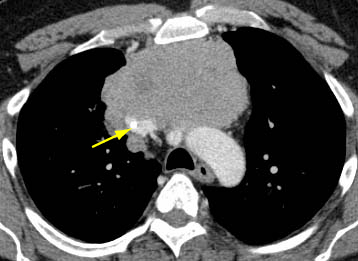

Quando o contraste intravenoso iodado é contraindicado, a ressonância nuclear magnética (RNM) do tórax pode ser usada para o estadiamento. Em geral, é menos útil que a TC porque os detalhes do tumor não estão definidos tão claramente. No entanto, a RNM com deslocamento químico pode ser útil na diferenciação entre hiperplasia tímica e tumor tímico.[26] Além disso, a RNM com sincronização cardíaca pode ser útil se houver suspeita de invasão cardíaca. A RNM também pode ser útil na diferenciação entre um tumor sólido e um cisto tímico benigno.[27] A PET-CT com fluordesoxiglucose (FDG) 18F pode ser usada para ajudar a diferenciar entre timoma (menos ávido por FDG) e linfoma (mais ávido por FDG) para tumores não invasivos distintos.[22] No entanto, se o tumor parece agressivo no exame de imagem, o resultado da PET não elimina a necessidade de uma biópsia percutânea com agulha grossa para diferenciar a neoplasia maligna tímica do linfoma, e para estabelecer um diagnóstico para terapia neoadjuvante ou terapia não cirúrgica definitiva.[28][29] A PET-CT também pode ser útil na demonstração de doença nodal ou metastática não suspeita; isso é útil quando os resultados de imagem ou histológicos sugerem um tumor agressivo.[30] De forma geral, à medida que a histologia da OMS se agrava, a intensidade de captação da PET (valor padronizado de captação) aumenta.[Figure caption and citation for the preceding image starts]: Tomografia computadorizada (TC) do tórax mostrando um típico timoma em estádio I de Masaoka-KogaDo acervo de Cameron Wright, MD; usado com permissão [Citation ends].